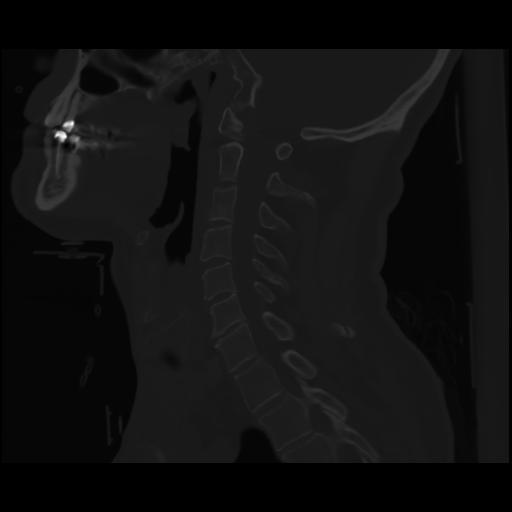

14 P.BLANDAS,,Sagittal,2.000,P.BLANDAS,Sagittal,